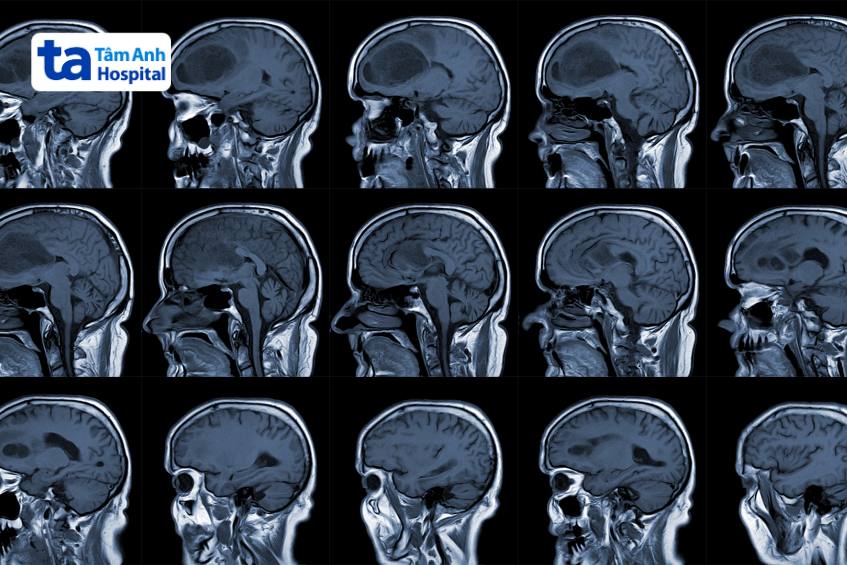

Các phương pháp chẩn đoán hình ảnh như chụp MRI, CT, DSA và sinh thiết định vị giúp xác định chính xác kích thước, vị trí và mức độ xâm lấn của khối u. Điều trị kết hợp phẫu thuật vi phẫu dưới kính hiển vi, phẫu thuật nội soi ít xâm lấn, phẫu thuật bằng Robot mổ não Modus V Synaptive ứng dụng trí tuệ nhân tạo, xạ trị và hóa trị trúng đích… giúp kiểm soát bệnh tốt hơn.